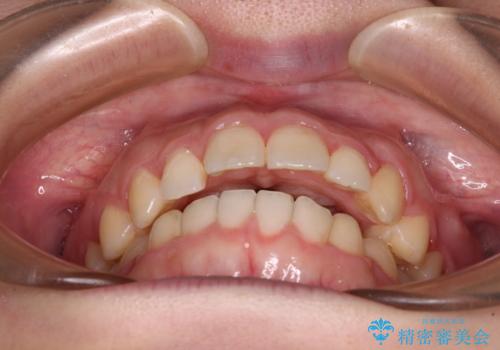

気になる残存乳歯と八重歯 ワイヤー矯正を併用したインビザライン治療

- 八重歯を気にして来院された患者様です。

八重歯のために乳歯が残存していたため、乳歯を抜去して八重歯となっている犬歯を歯列に収めることとしました。

八重歯の移動量が多くなるため、インビザラインと併用してワイヤー矯正を行い、八重歯を改善した後に、上下歯列をインビザラインで整えることとしました。

犬歯は歯根が長くて太いため移動に時間がかかる上に、周囲の歯が八重歯に寄ってきてしまうため、仕上がるまでに期間がかかりました。